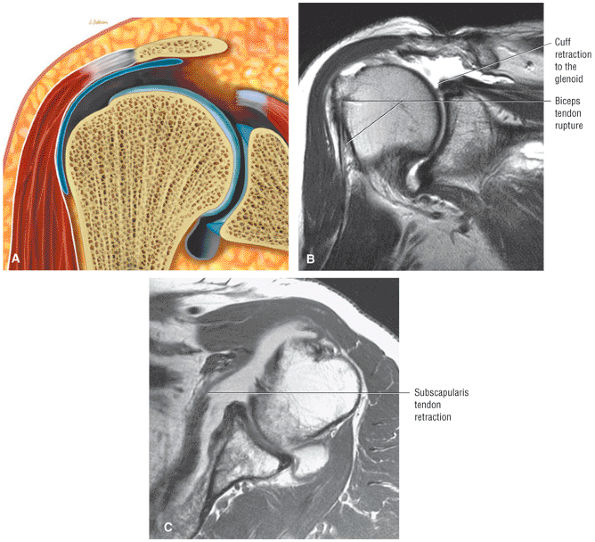

Rotator cuff tears should be measured in the coronal and sagittal planes.